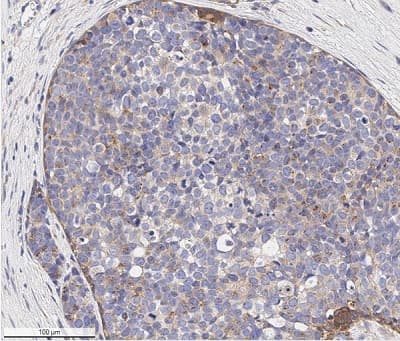

Anti-VEGF Receptor 1 + VEGF Receptor 2 antibody(ab36844)

Rabbit Polyclonal VEGF Receptor 1 antibody. Suitable for WB, IHC-P, ICC/IF and reacts with Mouse, Human samples. Cited in 9 publications. Immunogen corresponding to Synthetic Peptide within Mouse Flt1 aa 800-900.

Applications ICC/IF, IHC-P, WB

Species Reactivity Human, Mouse